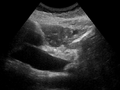

Dilatation of CBD due to Ampullary tumor.